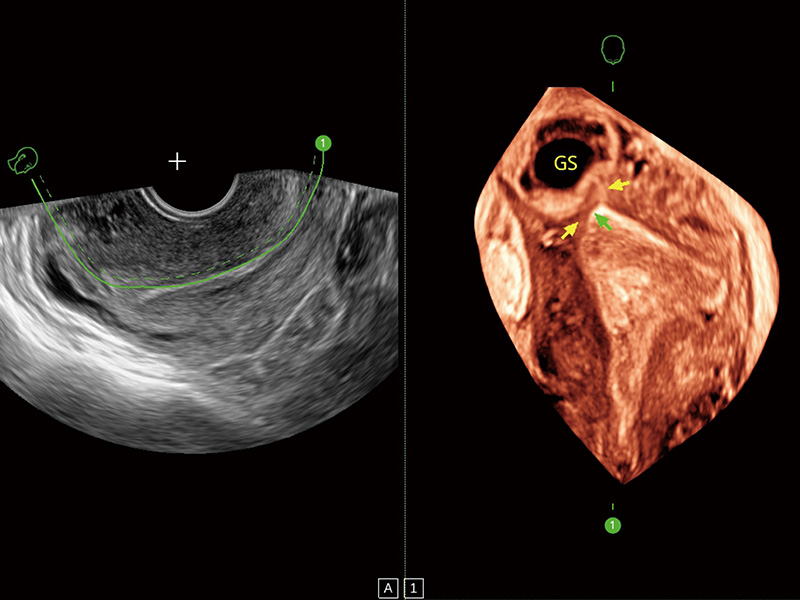

超声引导下胚胎移植

中央型宫腔粘连